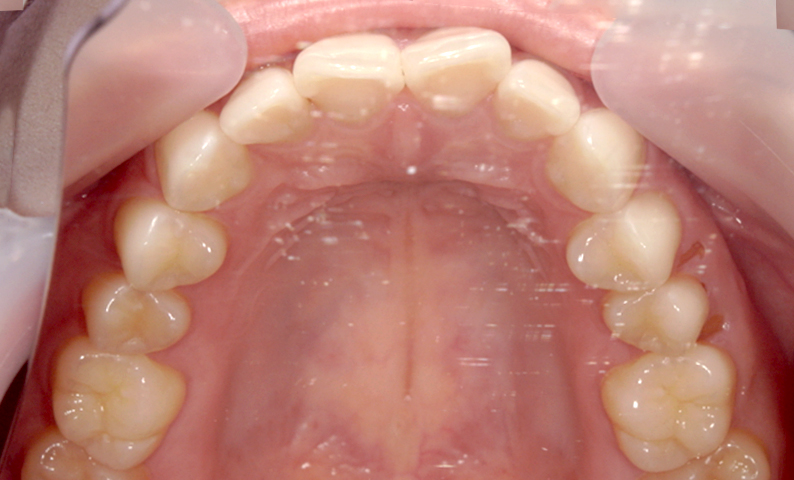

症例_002 前歯「捻転歯」症例

治療期間:7ヶ月金額:27万円+税20代女性少しのねじれ上の前歯だけ

| Before | After |